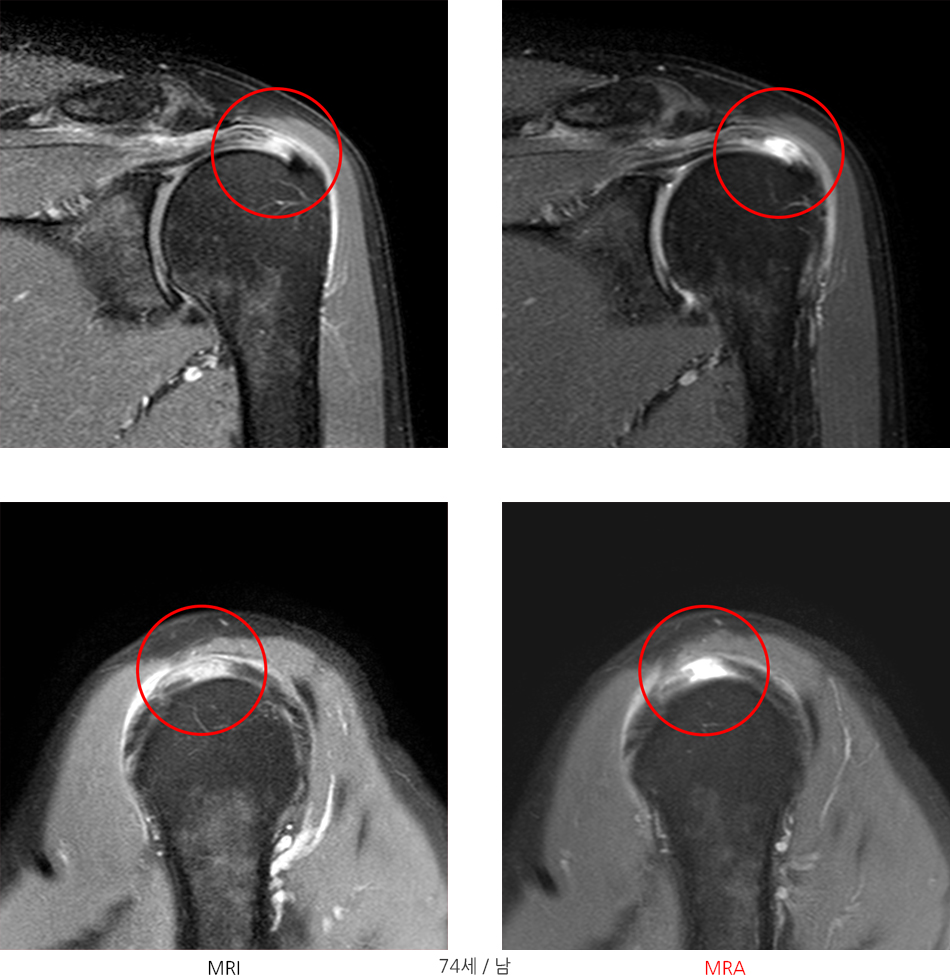

MRA(MR-Arthrogram)란, 관절 속에 조영제를 주입한 후 촬영하는 검사로, 관절와순이나 회전근개의 찢어진 틈으로 조영제가 스며들어가 파열 여부를 더욱 정확히 진단할 수 있게 됩니다.

※ MRI보다 MRA검사에서 명확하게 파열된 부분을 확인 할 수 있습니다.

※ MRA검사에서 관절와순 파열이 명확히 관찰되는 것을 확인 할 수 있습니다.